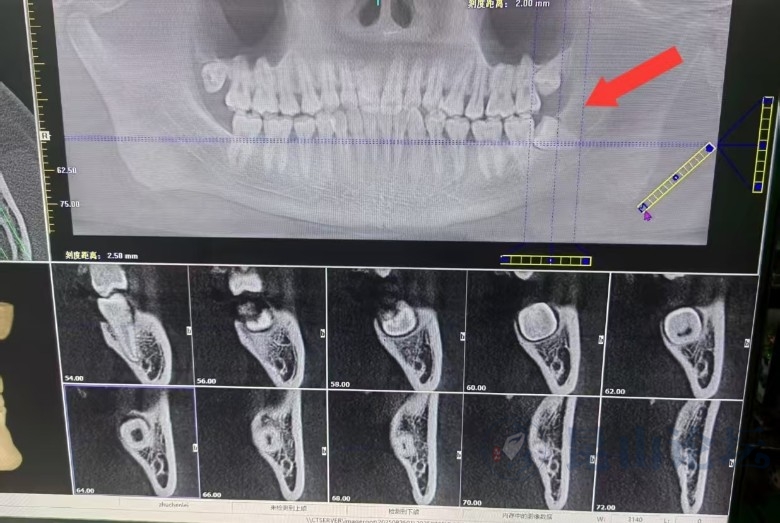

昆山哪里拔这种智齿水平好?

公立医院口腔科,这个8号位置最好挂副高以上的号,你的左上8不算太明显,右上8出来多点了

这颗牙还没长出来,在昆山杰齿拍的CT,说拔有一点困难。

不拔怕顶坏旁边的牙。